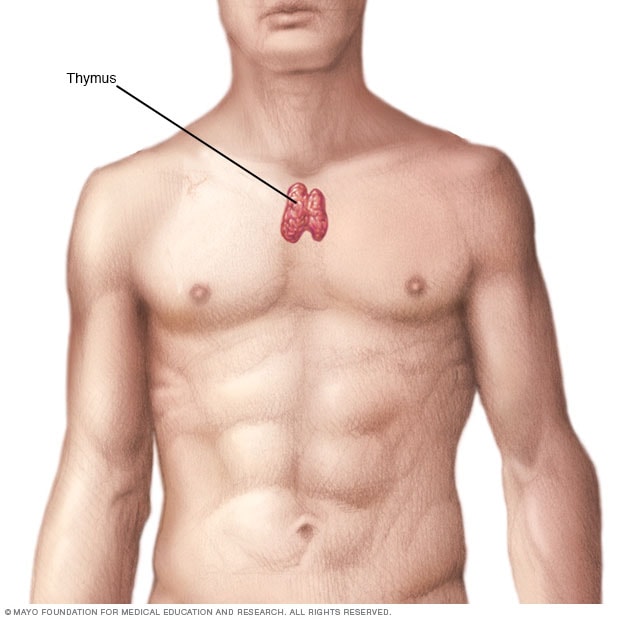

Тимомегалия: что это такое и как проявляется